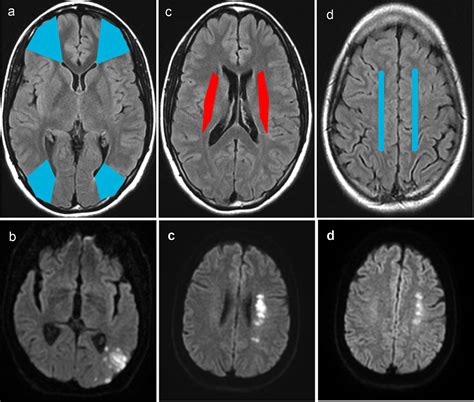

• Internal Watershed Zones: These occur deep within the brain, situated between the deep and superficial arterial systems. They are often associated with small vessel disease and chronic hypertension.

• Cortical Watershed Zones: These occur on the outer surface of the brain, specifically in the regions where the anterior cerebral artery (ACA) meets the middle cerebral artery (MCA), or where the MCA meets the posterior cerebral artery (PCA).

MRI (Diffusion-Weighted Imaging) The gold standard for identifying acute ischemic lesions in the border zones.